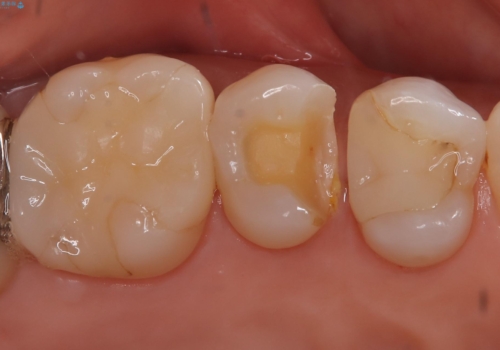

【セラミックインレー】昔治療した詰め物が外れた。

- 他院でいれたセラミックインレーが脱離して、来院されました。

新たに製作を希望されたため、当院で治療しました。

当院でのセラミックインレーの治療は、ラバーダムを使用しています。